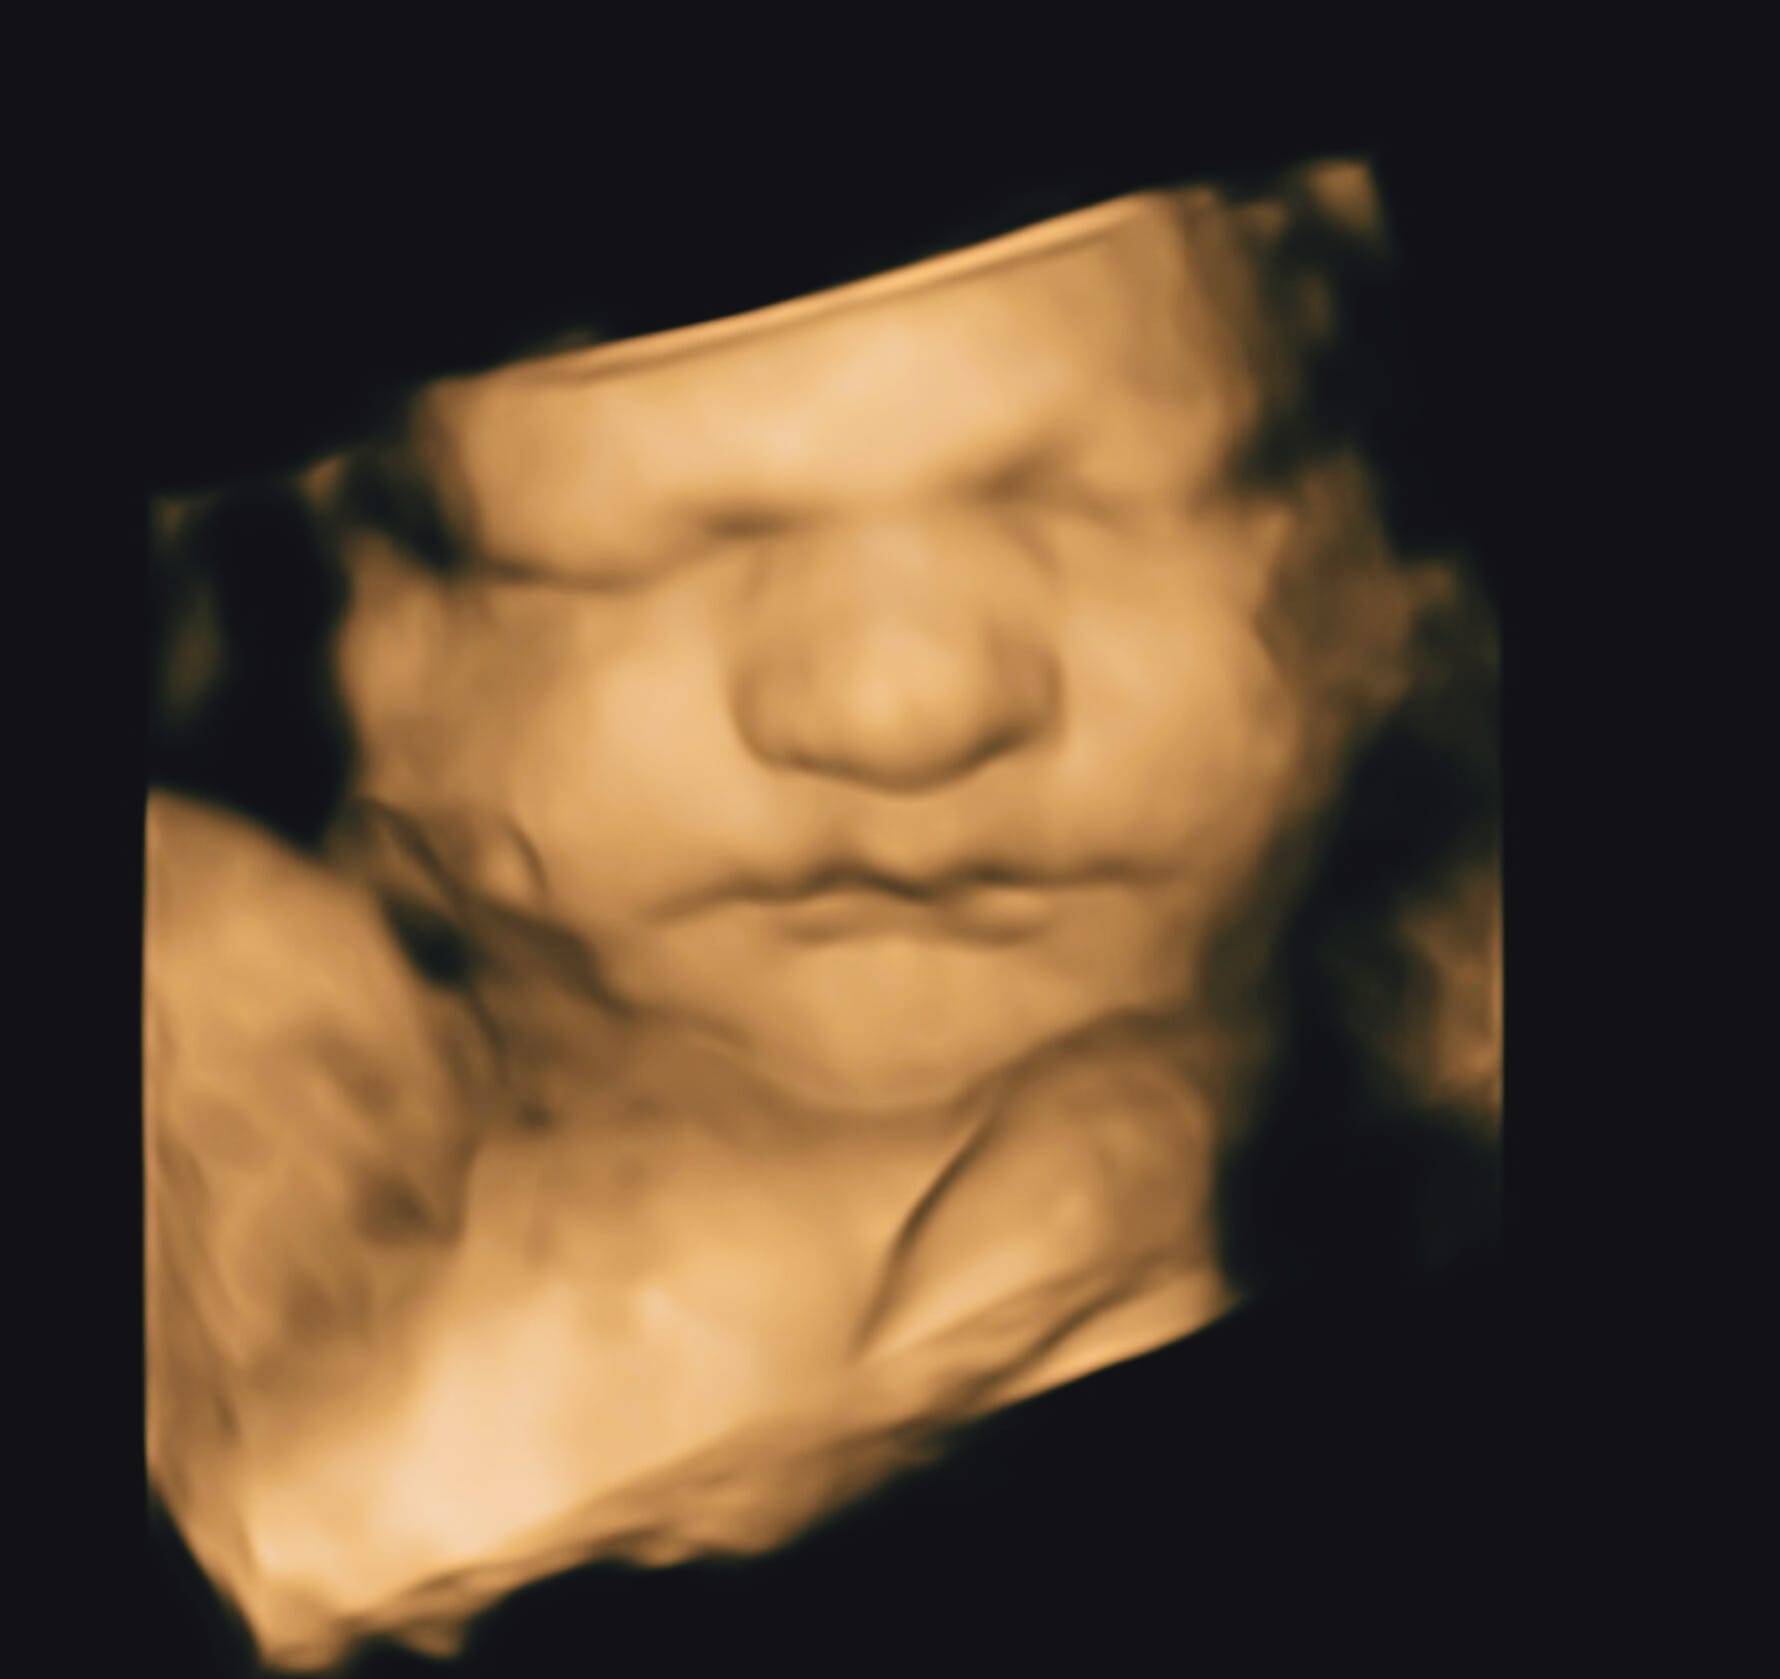

Venture on the journeying of maternity is an exciting and transformative experience. As you near the 16-week mark, you might be curious about what to expect, especially regarding your 16 week significant ultrasound. This milepost is significant for both you and your infant, as it volunteer a glimpse into your baby's maturation and overall health. Let's dig into the details of what you can await during this essential stage.

At 16 workweek, you are formally in your quaternary month of pregnancy. Your baby is grow rapidly, and your body is undergoing numerous alteration to back this growth. This workweek is oft tag by a routine prenatal check-up, which may include a 16 weeks meaning ultrasound. This echography is typically perform to value your baby's ontogeny and to insure for any likely matter.

A 16 hebdomad fraught ultrasound is usually a transabdominal ultrasound, meaning the technician will use a wand-like twist (transducer) that moves over your belly. This type of ultrasonography is non-invasive and painless. Hither are some key points to expect during the procedure:

• Purpose: The primary end of a 16 workweek pregnant ultrasound is to evaluate your babe's chassis and development. It help to confirm the due date, ensure the child's pump pace, and assess the placenta and amniotic fluid levels.

• Duration: The ultrasound commonly takes about 20-30 proceedings. You will lie on an interrogation table, and a gel will be applied to your stomach to heighten the persona quality.

• Image: You will be able to see your babe on the screen, and the technician may lead measuring and capture icon for your disk.

At 16 week, you are well on your way to welcome your little one into the world. The 16 weeks significant ultrasound is a important milepost that provides valuable insights into your baby's growth and overall health. Embracing this journeying with fervor and self-confidence, know that you are rear a new life with love and fear.